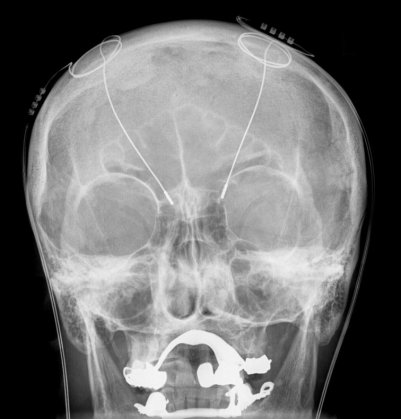

An example of DBS electrode placement.

Unfortunately, this form of DBS has a major downside: it necessitates seriously invasive brain surgery, which risks infection in the brain or damage to brain structures, potentially leading to loss of brain function, other complications, or even death [5,6]. Needless to say, a non-invasive method that could achieve the same specificity as DBS would be a preferable treatment.

X-ray image of implanted DBS electrodes.